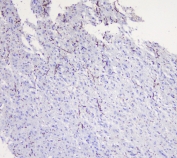

IHC staining of FFPE human glioma with MOG antibody at 1ug/ml. HIER: boil tissue sections in pH6, 10mM citrate buffer, for 10-20 min followed by cooling at RT for 20 min.